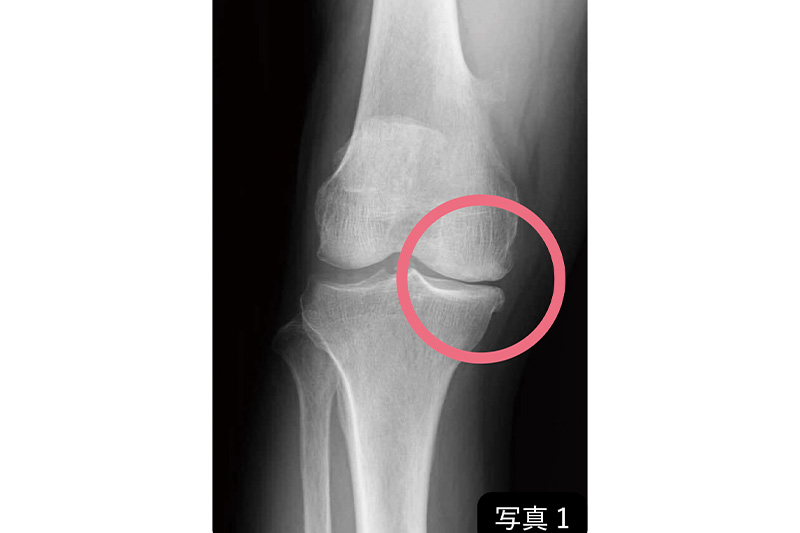

別掲の写真1を見てください。初期の「変形性膝関節症」の人のひざ関節の、立った状態のレントゲン写真です。関節の中を見ると、大腿骨と脛骨の間に隙間が見えます。

軟骨の成分は7割が水分なので、レントゲンには写りません。立って、ひざに体重をかけた状態でレントゲン撮影をして、大腿骨と脛骨の間に隙間があれば、それを軟骨の量と考えます。

写真1の隙間に注目すると、関節の外側の隙間を10とすると、内側の隙間は3ぐらいまで減っていますね。こうなると軟骨の間に挟まれた半月板は居場所が狭くなり、定位置からずれ、関節の外へ押し出されます。この患者さんも初診時ひざの痛みや、曲げ伸ばしのときに引っかかる感じを訴えていたので、半月板を損傷している可能性がありました。

ひざ関節の痛みや歩行のトラブルを訴えて病院に来る患者さんの約7割はこのケースと同じ、初期の状態の人です。この時期は半月板損傷による痛みが多い。

しかし、硝子軟骨は減ったものの残っているし、半月板もなくなったわけではありません。それぞれの連続性を回復させられたら、からだの「治る力」で治る(再生させられる)。写真1の「初期」の人は、Aパターンで軟骨が復活するというわけです。